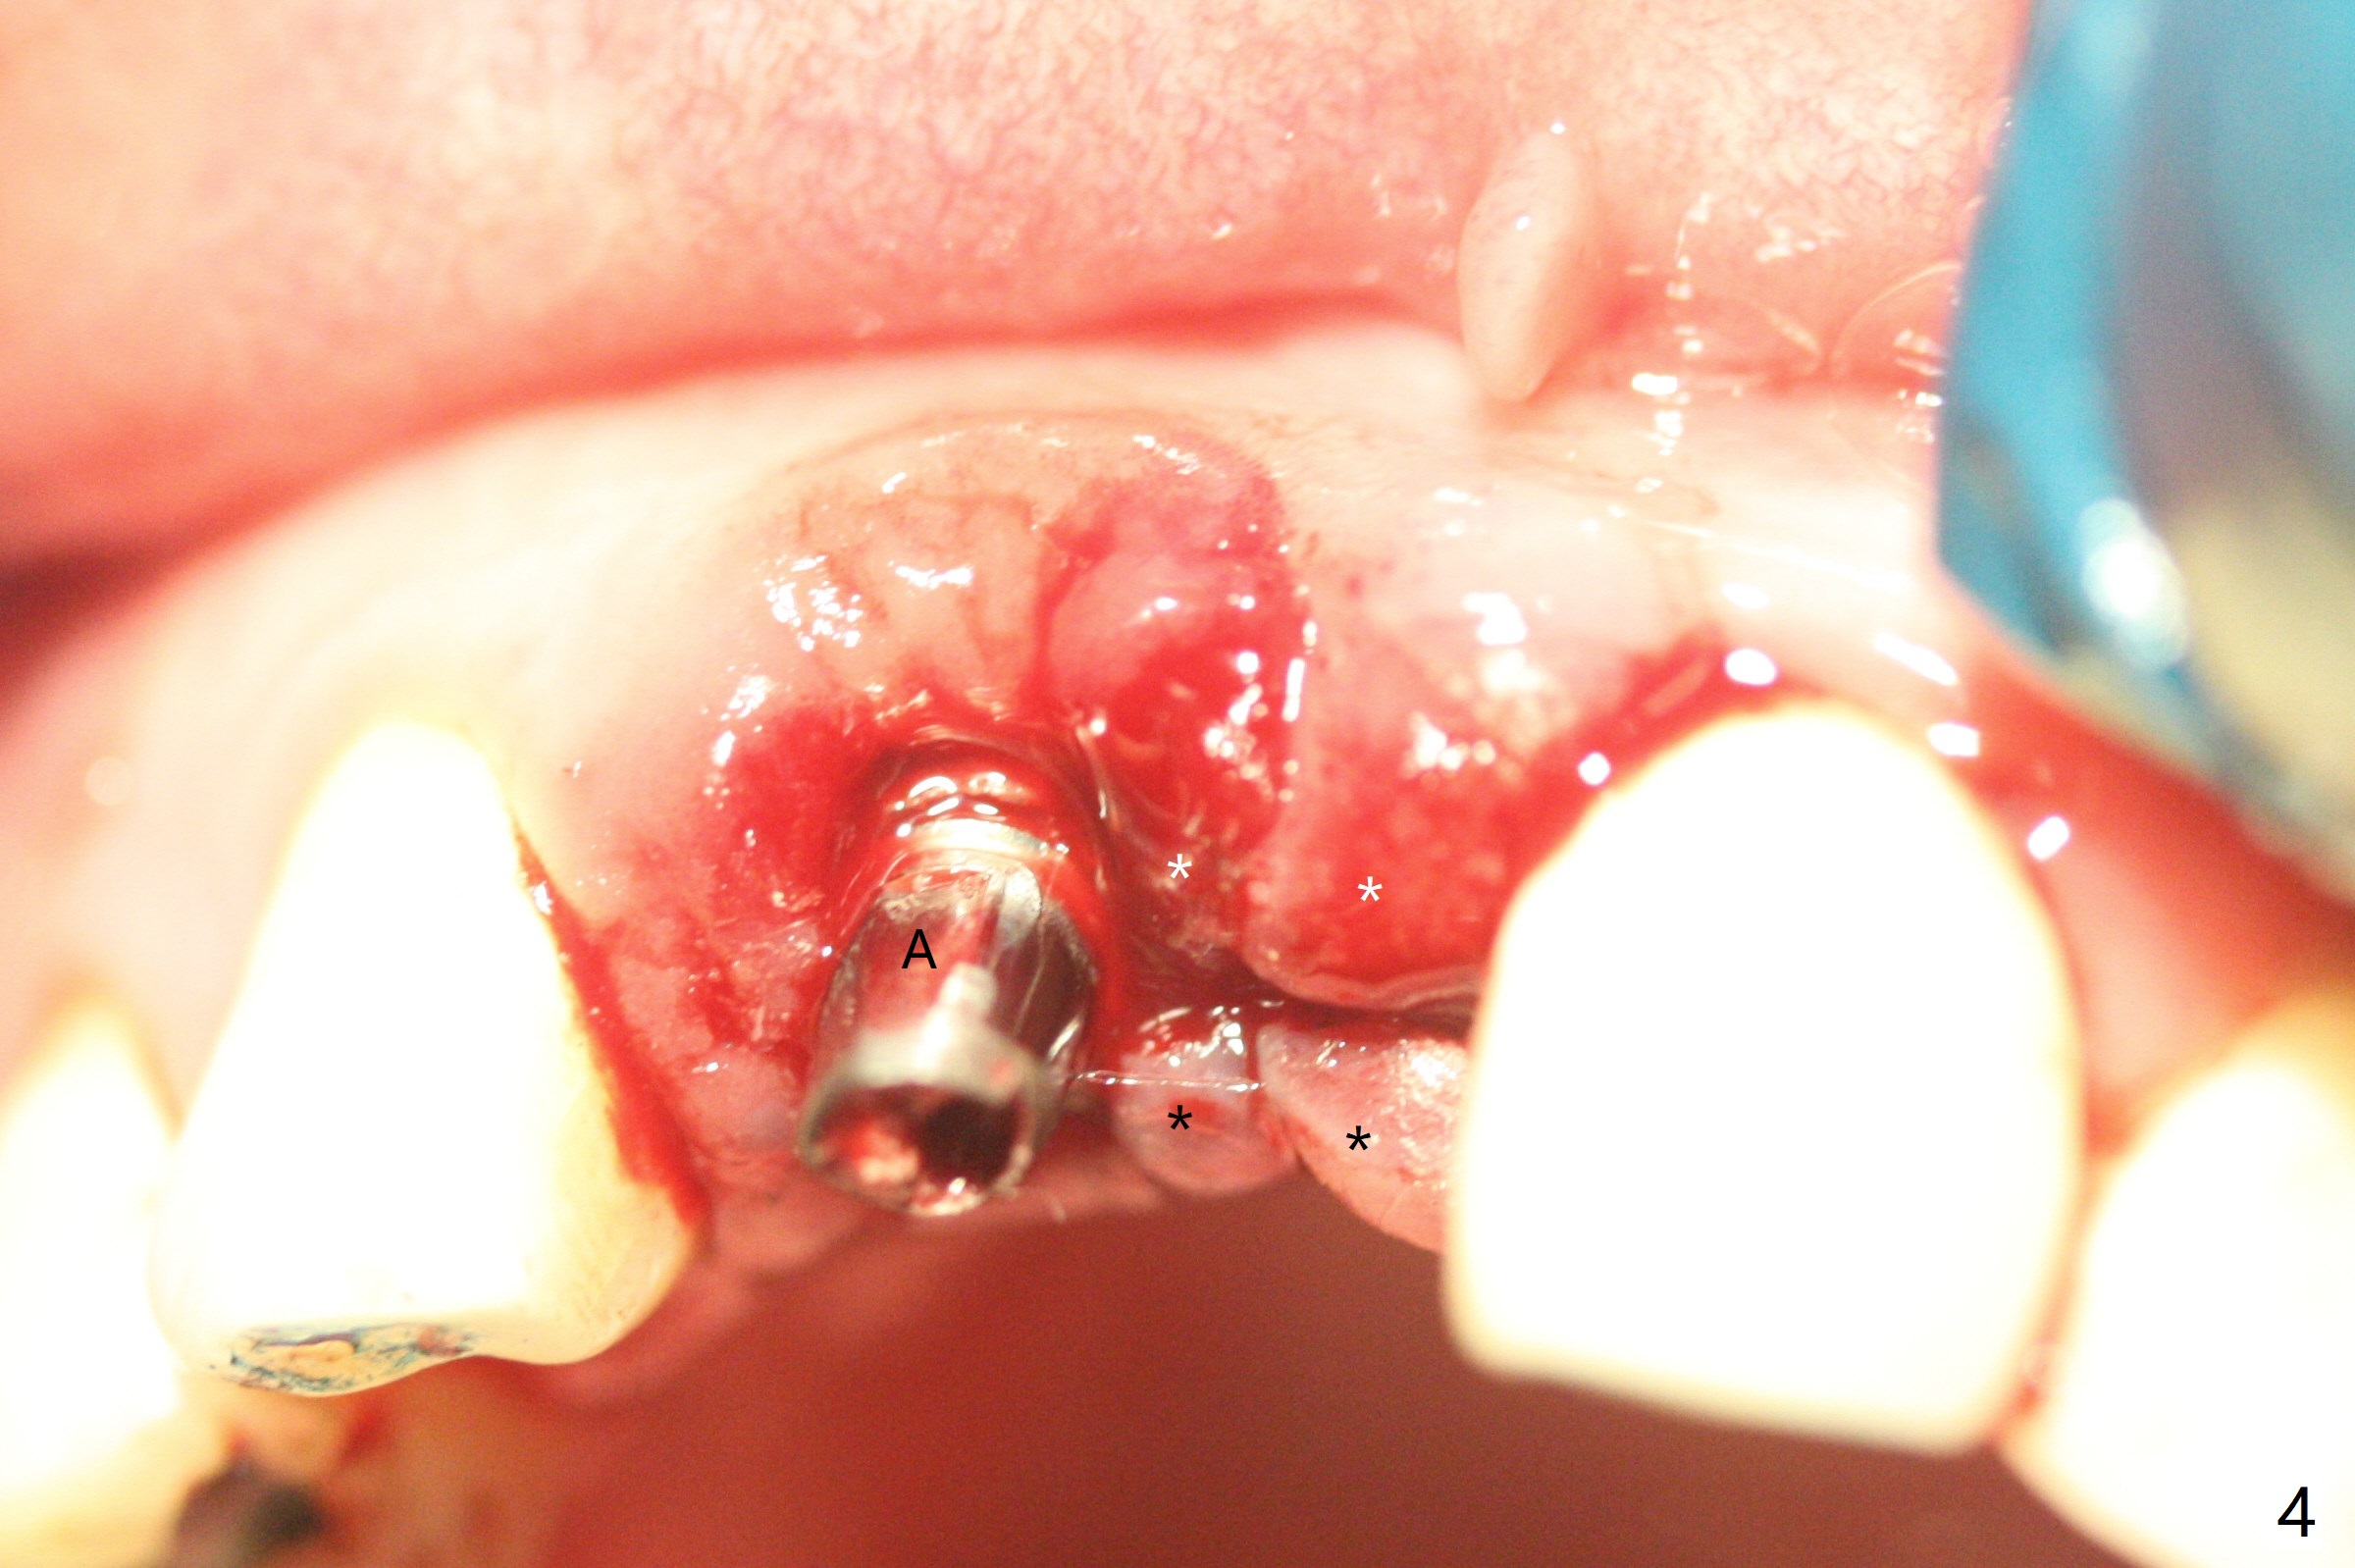

拆除部分桥发现:中,侧切牙牙龈红肿(图一),不利于切口和伤口愈合。不过还是在中切牙区切开,牙龈相当厚,有利于今后牙龈形成凹陷和乳头。坏消息是近远中距离太短,不利于植牙以及今后局部卫生维护,所以决定只在侧切牙种植(图二,三),完成钻洞后,颊侧根尖穿孔植骨,然后植入植体,即刻放置修复基台(图四 (*:牙龈乳头)),暴露基台牙龈缘,制作临时悬臂桥 (图五),两个中切牙牙冠长度差不多,插入临时桥时颊侧牙龈乳头基本形成(图六:*),缝合前颊侧,腭侧牙龈瓣下放置粘性骨块(图七,八:* )和PRF膜(图七:^)。最后使用牙周敷料。但愿术后牙龈炎症消失,形成良好牙龈乳头和pontic concavity。 其实由于口腔卫生习惯,术后十七天颊侧牙龈仍红肿(图九),而腭侧正常。如果口腔卫生改善而红肿依然存在,让实验室制作临时桥。术后一个月颊侧牙龈红肿好些(图十),好像骨粉丢失少许,可能与水枪使用有关。右上1牙冠显得太短(*)。也太肥大,因为右上1切缘太颊侧,与左上1对比(图十一:*)。由于颊侧牙龈(图十二:B)术中推向颊侧,与腭侧(P)牙龈之间放置大量粘性骨粉,术后一个月骨粉(<)形成牙龈,形成凹陷。颊侧萎缩不再明显了。右上1牙冠颈部多加些树脂,牙齿就显得长的多(图十三:箭头)。与侧切牙之间颈部故意留下间隙(*),让牙龈入位(空箭头),形成龈乳头。当右上1临时牙冠切缘(图十四:*)移到腭侧,外形改观不少。下次改善侧切牙唇侧。术后两个月三个星期牙龈红肿好像减轻,牙龈没有进入切牙间隙,干脆用树脂关闭(图十五:> <)。下次减少侧切牙切缘(^),适当增加中切牙长度(上提牙龈)。术后3.5个月植体好像整合,基台完全就位(图十六)。术后3.5个月Pontic凹陷形成,但是1,2之间龈乳头始终无法形成(图十七)。以后类似病例应该多种植一个。此例草率取模,可能需要临时粘固,观察植体近中颊侧所谓瘘道,必要刮治。由于比色不佳,需要实验室颜色更改,病人强化卫生,术后七个月,永久性牙冠粘固前,局部牙龈健康(图十八)。